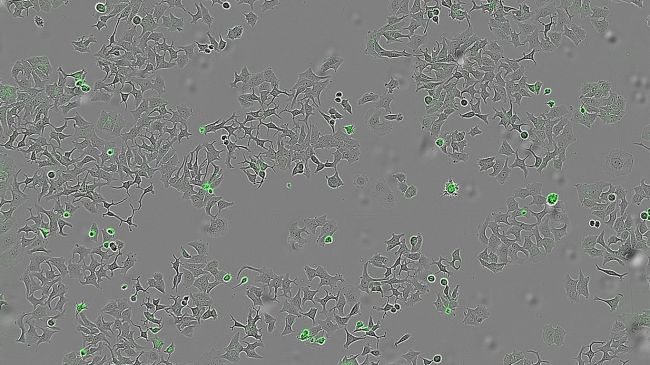

یورونیوز: بر پایه پژوهشی که گروهی بین‌المللی از دانشمندان به سرپرستی محققان اسپانیایی ‏انجام داده‌اند، نوعی باکتری خاص پروتئینی ترشح می‌کند که می‌تواند باعث خودتخریبی ‏سلول‌های سرطانی شود و احتمالاً راه را برای درمان‌های جدید هموار کند‎.‎

بنا بر این مطالعه که در نشریه Cell Death Discovery منتشر شده است، این پروتئین امیدبخش که HapA نام دارد، توسط باکتری عامل بیماریِ «وبا» ترشح می‌شود. پژوهشگران این مکانیسم جدید را در سلول‌های غده‌های پستانی، روده بزرگ و پانکراس مورد آزمایش قرار داده‌اند.

تیم پژوهشی با انجام آزمایش‌هایی روی گونه‌های جهش‌یافته وبا که فاقد این پروتئین بودند همچنین روی نوع دیگری از باکتری که به‌صورت ژنتیکی طوری تغییر یافته بود که فقط HapA تولید کند، نشان داد که تنها در حضور HapA، زنده‌مانی سلول‌های توموری کاهش می‌یابد.

آن‌ها همچنین بررسی کردند که آیا HapA در برابر انواع مختلف غده‌های سرطانی مؤثر است یا نه، و برای این کار مایعی حاوی تمام پروتئین‌های ترشح‌شده توسط باکتری را روی رده‌های سلولی سرطان پستان، روده و پانکراس اعمال کردند.

هورتادو گفت: «ما می‌خواستیم ببینیم آیا سلول‌های انسانی از انواع مختلف غده سرطانی، پس از تماس با این مواد باکتریایی، به‌ویژه با پروتئین HapA، باز هم زنده می‌مانند و می‌توانند تکثیر شوند یا نه.»